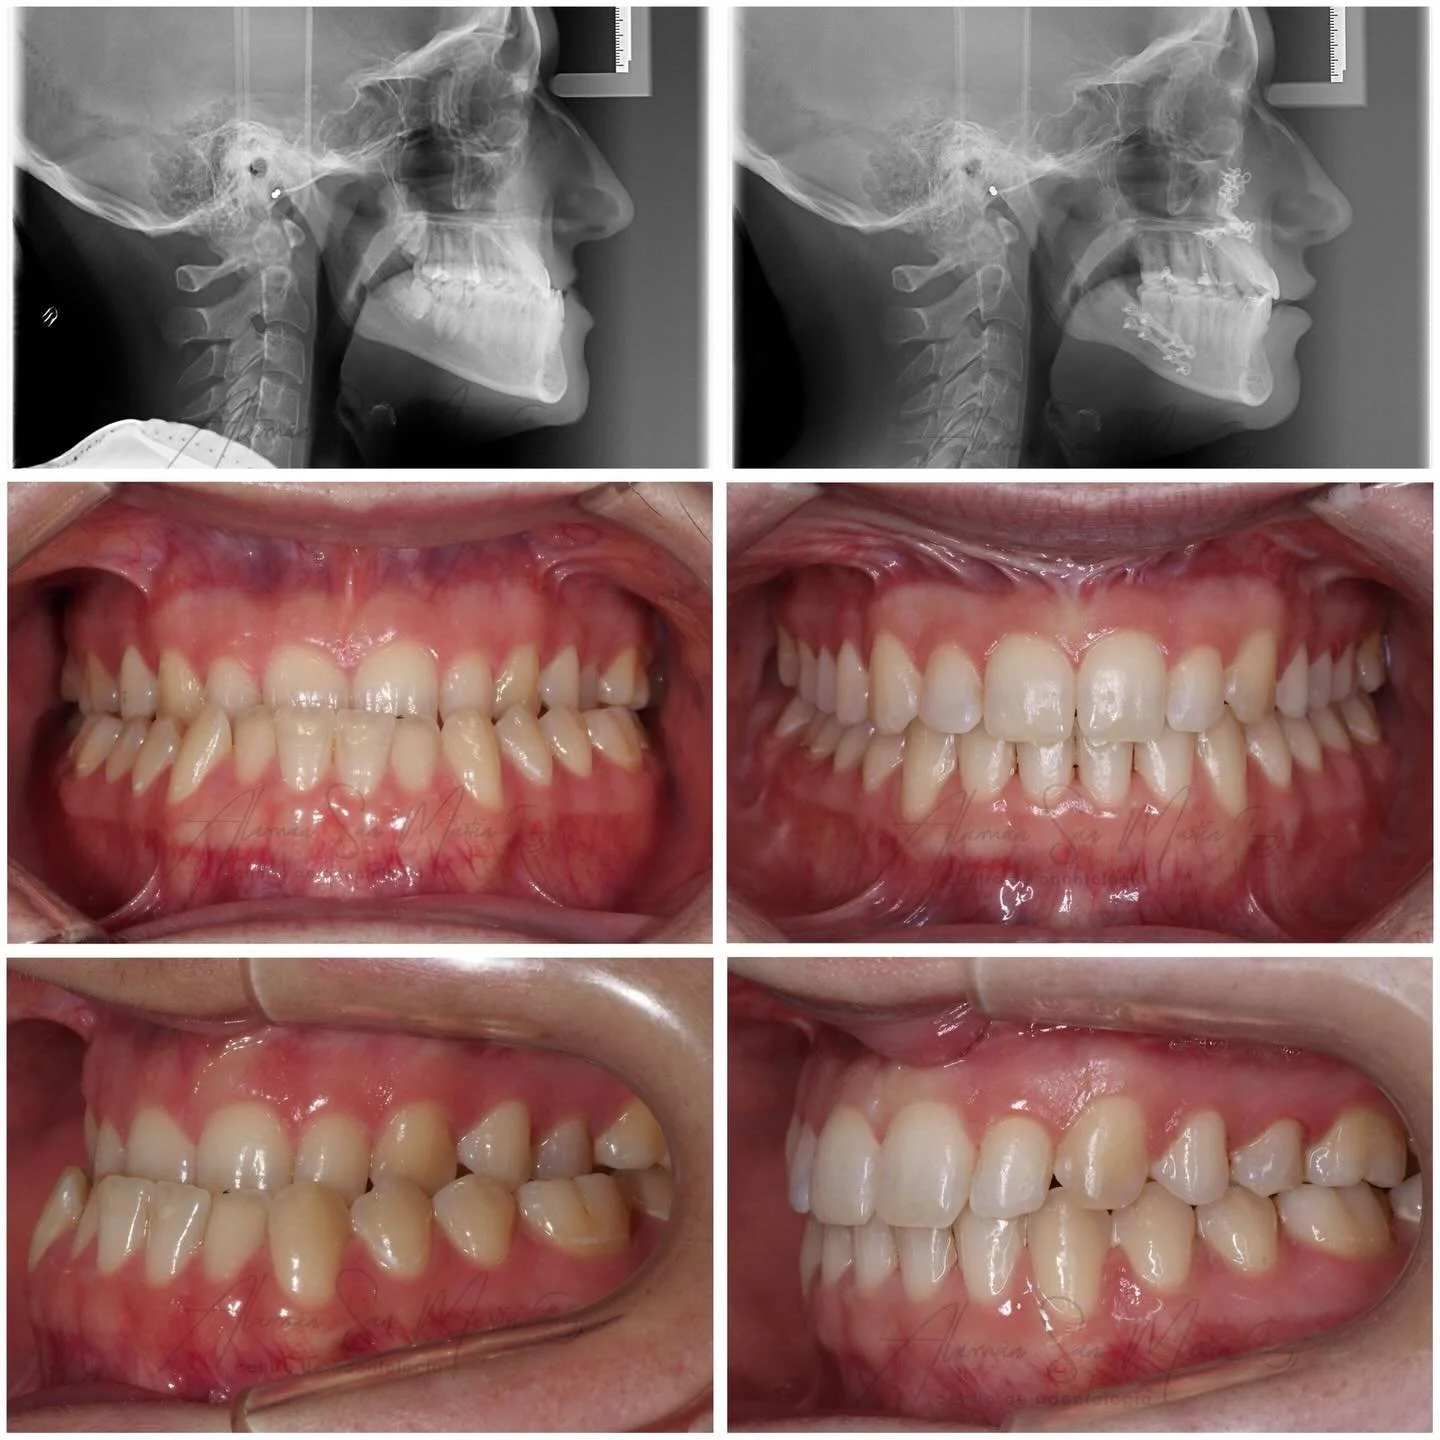

A nuestra clínica acuden muchos pacientes remitidos de los servicios de Cirugía Maxilofacial de los Hospitales de Madrid con problemas óseos y de maloclusión oseodentaria grave que requieren una preparación de ortodoncia antes de la Cirugía Ortognática en su Hospital.

En la clínica se realiza Ortodoncia Quirúrgica en adultos desde 1998, con excelentes resultados gracias al trabajo de los Cirujanos Maxilofaciales en combinación con nuestra Ortodoncia y la exacta preparación de las Férulas Quirúrgicas por nuestros protésicos.

La Ortodoncia Prequirúrgica cambia las inclinaciones de los dientes y consigue una buena forma de arcada sin apiñamiento para que haya una oclusión estable en la cirugía.

La Ortodoncia Postquirúrgica mantiene la posición ósea obtenida con la cirugía y termina de conseguir la mejor oclusión equilibrada posible en el paciente.